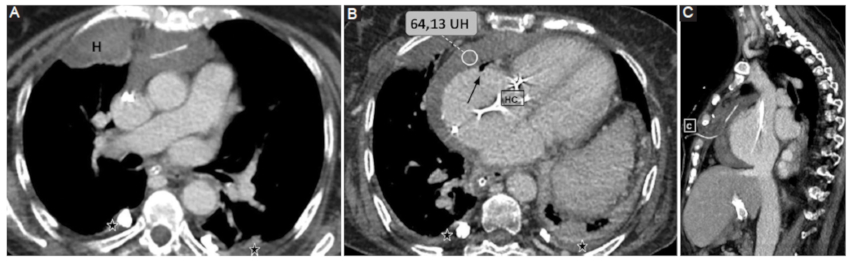

Por su parte, el análisis de la densidad del DP resulta una herramienta complementaria útil y accesible. Se ha estudiado la composición del DP por medio de la medición de densidades tomográficas y su correlación con los datos del análisis bioquímico. En este sentido, una densidad promedio similar a la del líquido es indicativa de trasudado, mientras que valores mayores a 20 UH se vinculan con exudados y mayores a 50 UH con contenido hemático con alta especificidad (Fig. 1) (3,7.

Iatrogénico: en este grupo se engloban el hemopericardio secundario a procedimientos cardiacos invasivos tales como la intervención coronaria percutánea o la colocación de marcapasos (Fig. 9); o como consecuencia de una cirugía cardiovascular (Fig. 10).

Trauma torácico: fuerzas de alta energía que llevan a la presencia de hemopericardio, ruptura pericárdica, taponamiento cardiaco y/o herniación.

Síndrome aórtico agudo: en este contexto, el hemopericardio ocurre con una frecuencia estimada de entre un 17-45%, hecho que contraindica la pericardiocentesis y representa una emergencia clínica (Fig. 11) (6.

Los métodos por imágenes están indicados para la valoración de cuantía y severidad con un nivel de evidencia B clase 1 según las guías vigentes6. Según la serie de Rifkin et al. (3, la TCMC, entre otras cosas, permite identificar la presencia de hemopericardio ante una densidad promedio mayor a 30 UH con una sensibilidad cercana al 100%.